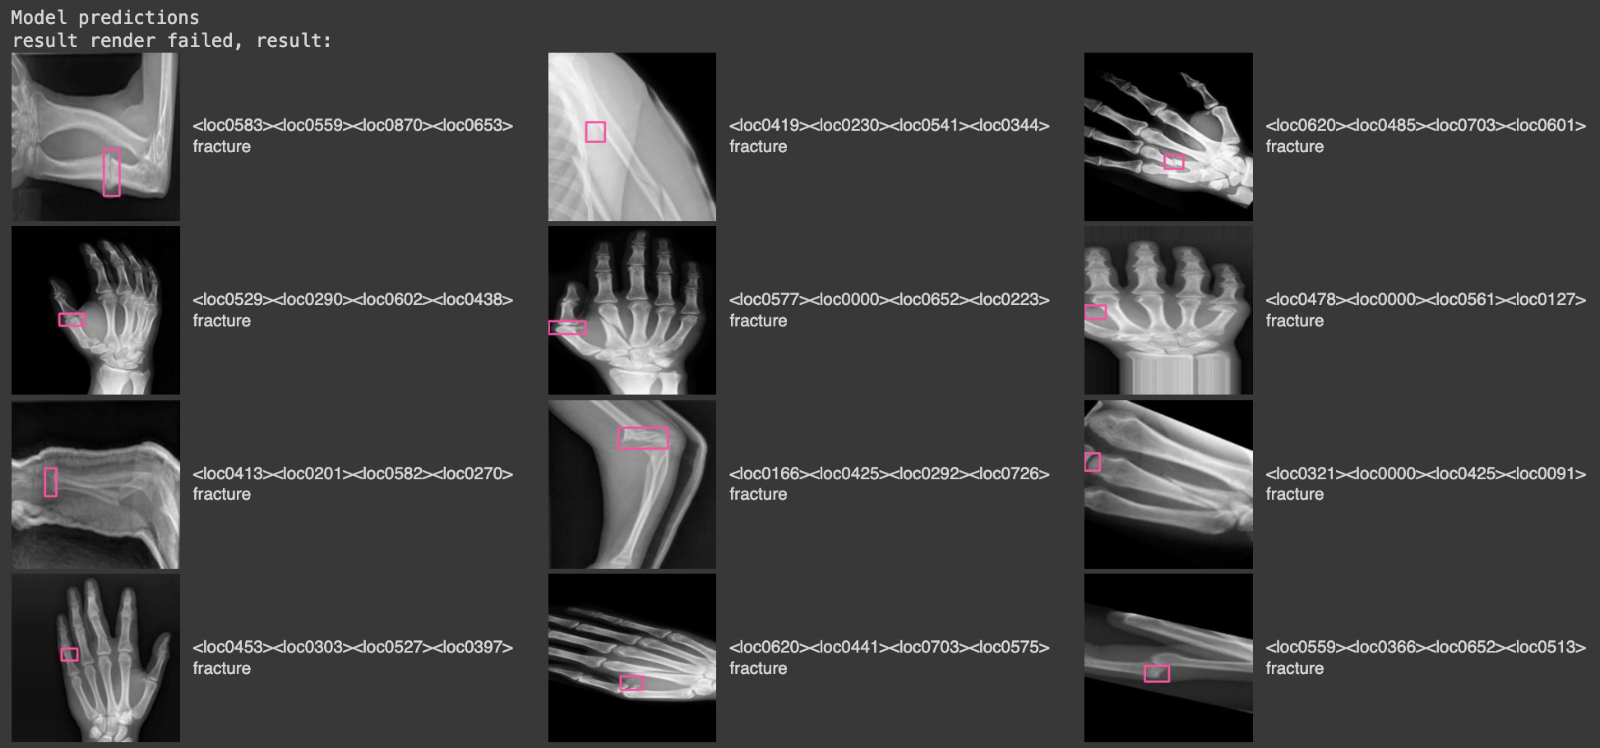

display(HTML(html_out))Here is a selection of results from our model when run on the validation dataset for our project:

In this image, there are images from the validation set, with pink bounding boxes that correspond to detections from the model, and text labels on the right that tell us what class was identified ("fracture").